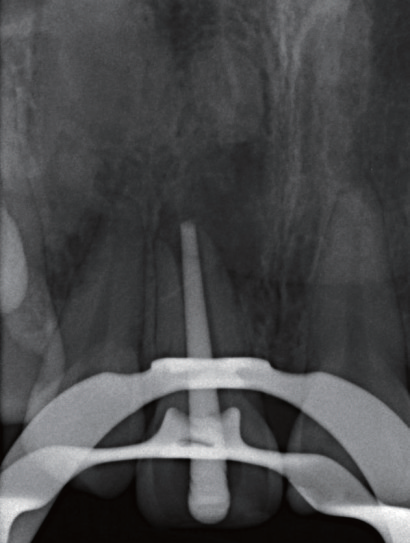

图8 11根管预备后用牙胶尖探出根尖口,发现根尖病灶区里虽无脓液也无新鲜血液

图9 由于11 根尖未闭合,试主尖时始终得不到理想回拉阻力

图10 以自制MTA 覆满的牙胶尖,尝试封闭呈喇叭状开口的根尖

图11 运用施德氏根充法,将特制牙胶尖压实

图12 不断重复加热、软化覆满MTA 的牙胶尖,以垂直加压法将其填满根尖